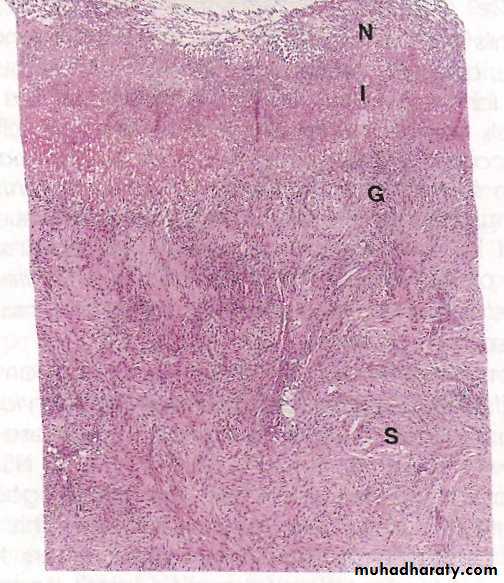

microscopically

• 4 zones distinguished:• The base and margins have a thin layer of necrotic fibrinoid debris.

• Underlain by zone of active nonspecific infl infiltrate, with neutrophils predominate.

• Underlain by granulation tissue.

• Fibrous collagenous scar that fans out widely from the margin of the ulcer.